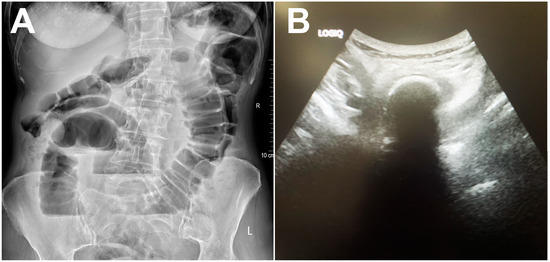

| Calcified bezoar (“Bezoar egg”) | Hyperechoic oval structure with posterior acoustic shadow within the bowel lumen | Oval, clearly demarcated mass with centrally placed gas | T1w and T2w hipointense oval mass with layered structure |